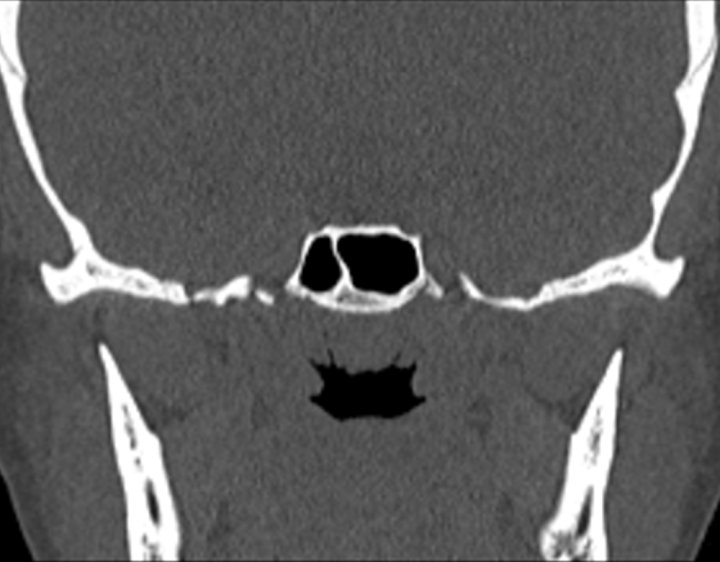

Click any image for labels.